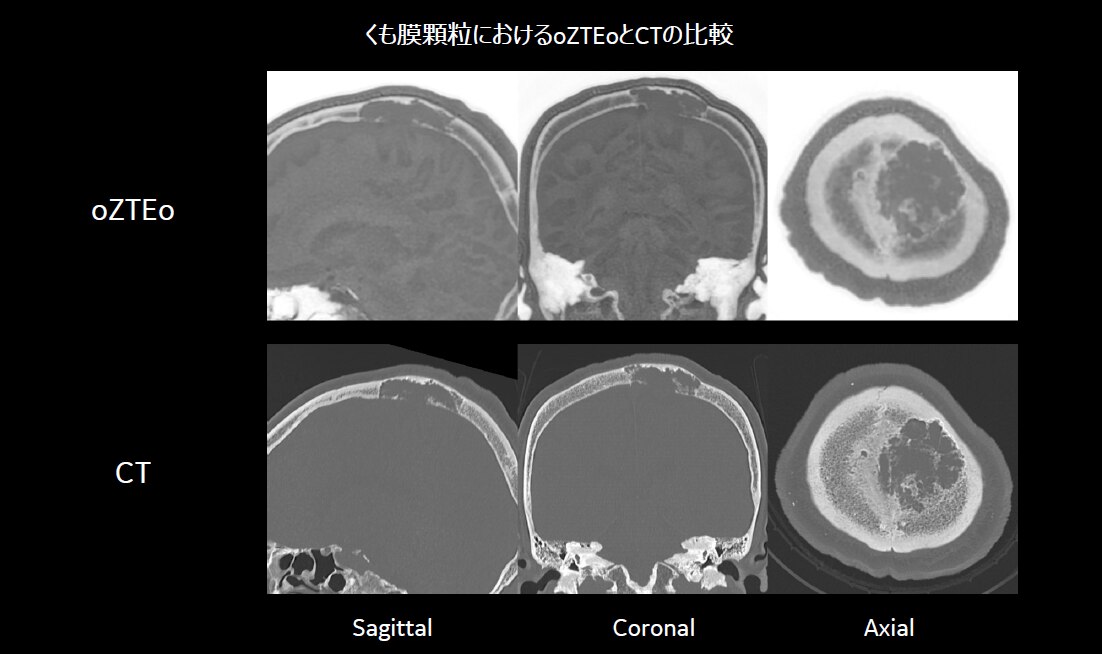

◆ Case1. くも膜顆粒(arachnoid granulation)

病変部位の形状変化を経過観察する必要があるが、その後のフォローアップではMRIにて検査を実施している。長期間の経過観察を行っている患者については、MRIのみでのフォローアップへの切り替えが可能となると考えている。骨腫瘍においては、短期間にサイズが増大することで悪性腫瘍の可能性が出てくると言われており、徐々に大きくなる場合は良性の可能性も含まれる。そのため、腫瘍サイズの経時的な確認が重要となる症例である。

脳神経外科医からは、「これらCase1、2、3の症例は全てCTとMRIの両検査にて経過観察中であった症例であるが、oZTEoによって骨情報の取得が可能になったことで、病変の大きさ、形状変化に対しての診断はMRIのみで可能である。」とコメントをもらっている。症例によってはCTを省略し、MRIのみでの評価が可能であり、患者負担を軽減することが期待できる。